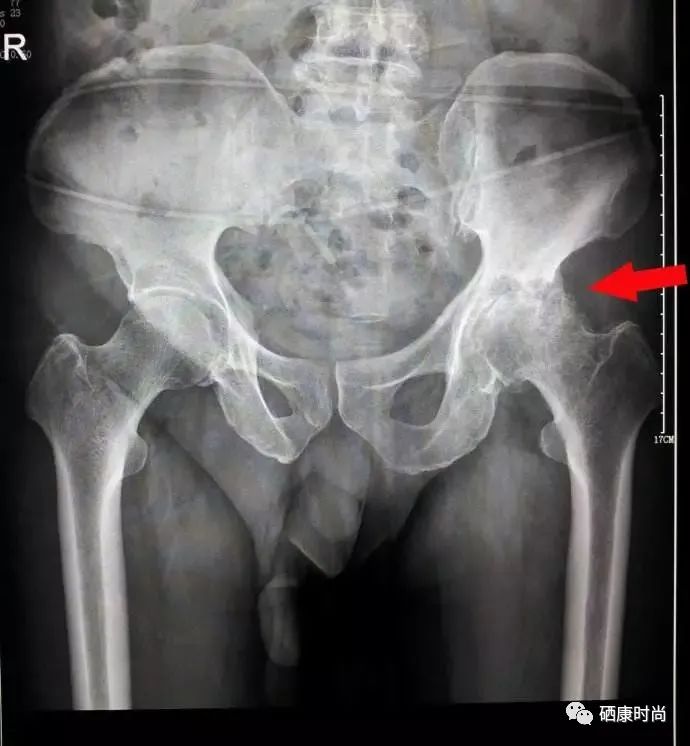

第一种是外伤性原因:包括股骨颈骨折,髋关节脱位。经常这两种创伤可以导致股骨头的血供遭到破坏,从而出现股骨头缺血性坏死。

第二种是非外伤性因素:常见的是长期大量使用类固醇激素,长期饮酒,这两种因素会导致脂肪代谢异常,出现股骨头供血血管堵塞,从而出现股骨头坏死。其他的一些发病原因还包括先天性髋关节发育不良、强直性脊柱炎、潜水病、系统性红斑狼疮以及一些血液系统疾病等。

总结这些发病原因不难看出,去除先天,骨折和骨结核,剩下这些大部分都和小动脉血管阻塞,微循环障碍有关!股骨头坏死的罪魁祸首就是血管堵塞,导致股骨头失去血运供养而出现萎缩 和骨膜裂纹。最初股骨头位置出现放射性疼痛,一直到膝盖位置,进而髋关节活动受限。

股骨头坏死在医学界称为“不死的癌症”无药可治!

生活中股骨头坏死的发病率是很高的,生活中有很多人会患上这种骨科疾病,给患者带来了极大的痛苦身体上和精神上双重折磨。来自身体是24小时疼痛!精神上是家庭生活造成极大隐患!目前医学保髋没有很好的药物手段,只能到后期手术置换股骨头或者全髋置换。

股骨头坏死Ⅰ Ⅱ Ⅲ患者每日清淡饮食,戒烟,戒酒,避免激素类药物,不要负重。还要补充钙 锌 硒等元素,硒是人体血液的清道夫,能把血液中有害物质,脂质过氧化物,过氧化氢,自由基等清除出去,防止血管壁膜的损伤引发血栓形成。堵塞股骨头血运供养,恢复血管通畅减轻疼痛,降低损伤,防止塌陷,有利于恢复!